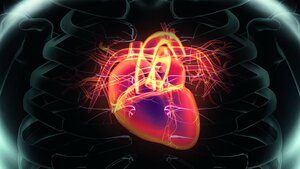

Premium Kardiologie 01.11.18 Sabrina ErtmerMyokardinfarkt Physiologie und Pathophysiologie Die Blutversorgung des Herzmuskels wird durch die Koronararterien (Herzkranzarterien) gewährleistet.…